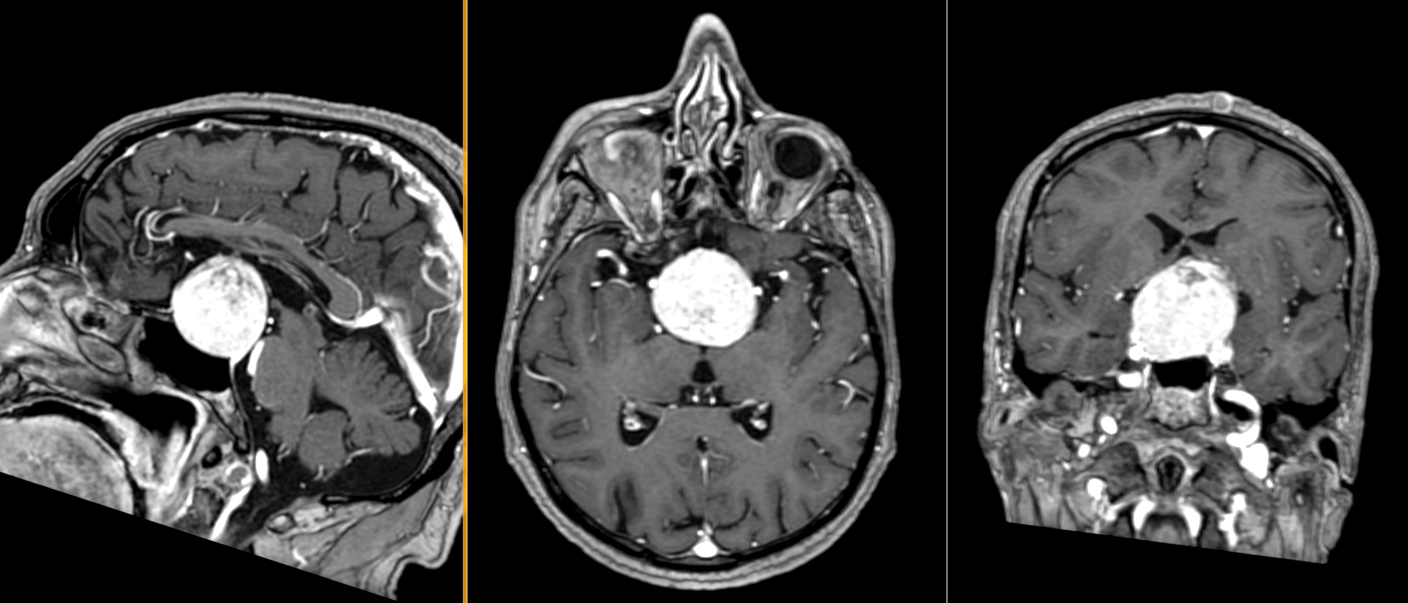

Localizare și creștere tumorală

Craniofaringioamele au localizare predominant supraselară, dar pot avea extensii variabile în zona selară, hipotalamică, chiasmatică și ventriculară. Frecvent, tumora comprimă structurile din vecinătate, inclusiv hipotalamusul, hipofiza, chiasma optică, arterele cerebrale anterioare și ventriculii laterali. Această poziționare explică simptomatologia complexă, care poate include tulburări endocrine, neurologice și vizuale.

- Imagistica cerebrală (RMN și CT) este esențială. RMN-ul evidențiază tumora în detaliu, oferind informații despre extindere și relațiile cu structurile adiacente. CT-ul evidențiază mai bine calcificările caracteristice craniofaringioamelor adamantinomatose.

Chirurgia endoscopică transsfenoidală este preferată atunci când tumora are o localizare predominant selară și supraselară inferioară.